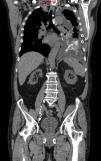

Un varón de 71 años consultó por disnea progresiva de dos semanas de evolución, sin síntomas generales, ortopnea, fiebre ni traumatismo previo. Entre sus antecedentes destacaban hipertensión arterial, fibrilación auricular no valvular permanente y un recambio valvular aórtico con prótesis mecánica realizado ocho años antes. Seguía tratamiento con acenocumarol. En la radiografía de tórax se observó un derrame pleural izquierdo que ocupaba la mitad del hemitórax. Una toracocentesis mostró un líquido lechoso con las siguientes características: leucocitos 1.875/μL (95% de linfocitos), proteínas 3,8 g/dL (suero 6,91 g/dL), lactato deshidrogenasa 373 U/L (suero 685 U/L), triglicéridos 1.203 mg/dL (suero 93 mg/dL), colesterol 62 mg/dL (suero 197 mg/dL), citometría de flujo normal y estudios citológicos negativos para malignidad. Una tomografía computarizada toracoabdominal sólo objetivó el derrame pleural izquierdo sin engrosamientos pleurales ni adenomegalias. Una linfangiografía intranodal evidenció una extravasación del material de contraste (lipiodol) hacia la cavidad pleural izquierda (fig. 1). Al re-interrogatorio dirigido, el paciente refirió varios accesos de estornudos intensos durante los días previos a la aparición de los síntomas actuales, extremo que confirmó su esposa. El paciente requirió dos toracocentesis terapéuticas de 1 L y 1,25 L en el trascurso de dos semanas, por lo que se insertó un catéter pleural tunelizado (CPT) para drenaje controlado en domicilio. Después de dos semanas de vaciamiento intensivo (diario) a través del CPT y tras confirmarse la re-expansión pulmonar radiológica, se instilaron 4 g de talco en solución (slurry) a través del CPT. Simultáneamente se recomendó restricción de dietas grasas y se prescribió octeótride (50 mcg/12 h sc), que se mantuvo durante seis semanas. Pasadas 10 semanas desde la instilación del talco a través del CPT y tras tres drenajes sucesivos inferiores a 50 mL se retiró el CPT. No se ha observado recidiva radiológica del derrame después de un año de seguimiento.